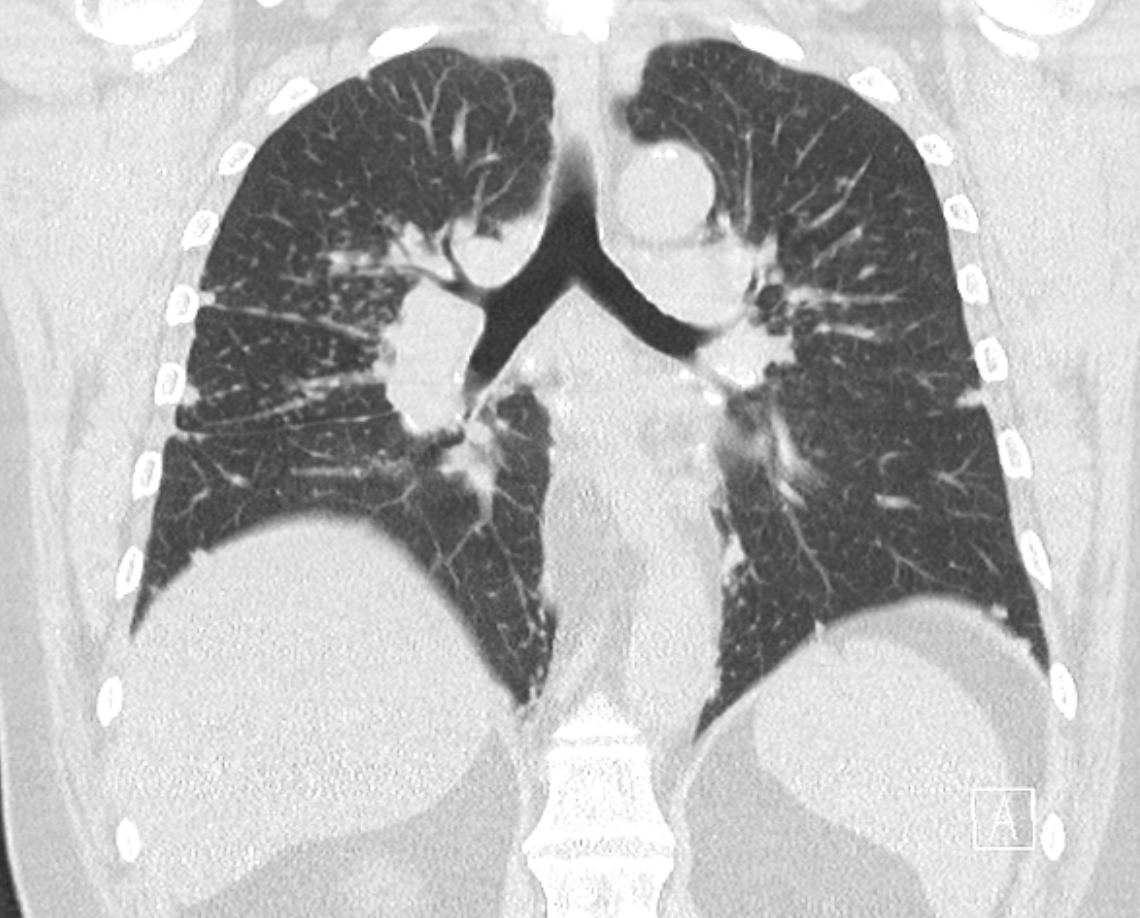

M25 Low-grade fever, cough, shortness of breath with a history of bronchial asthma, eczema at hands and feet, nasal polyposis, and past episode of pericarditis.

Picture: Typical symtpoms of eosinophilic granulomatosis with polyangiitis are present (e.g. chronic nasal polyposis, past pericarditis and onset respiratory symptoms). Imaging illustrates a ground glass pattern compatible with eosinophilic pneumonia and, in addition to this, laboratory findings (peripheric eosinophilia, BAL with high count of eosinophils) confirm the diagnosis.